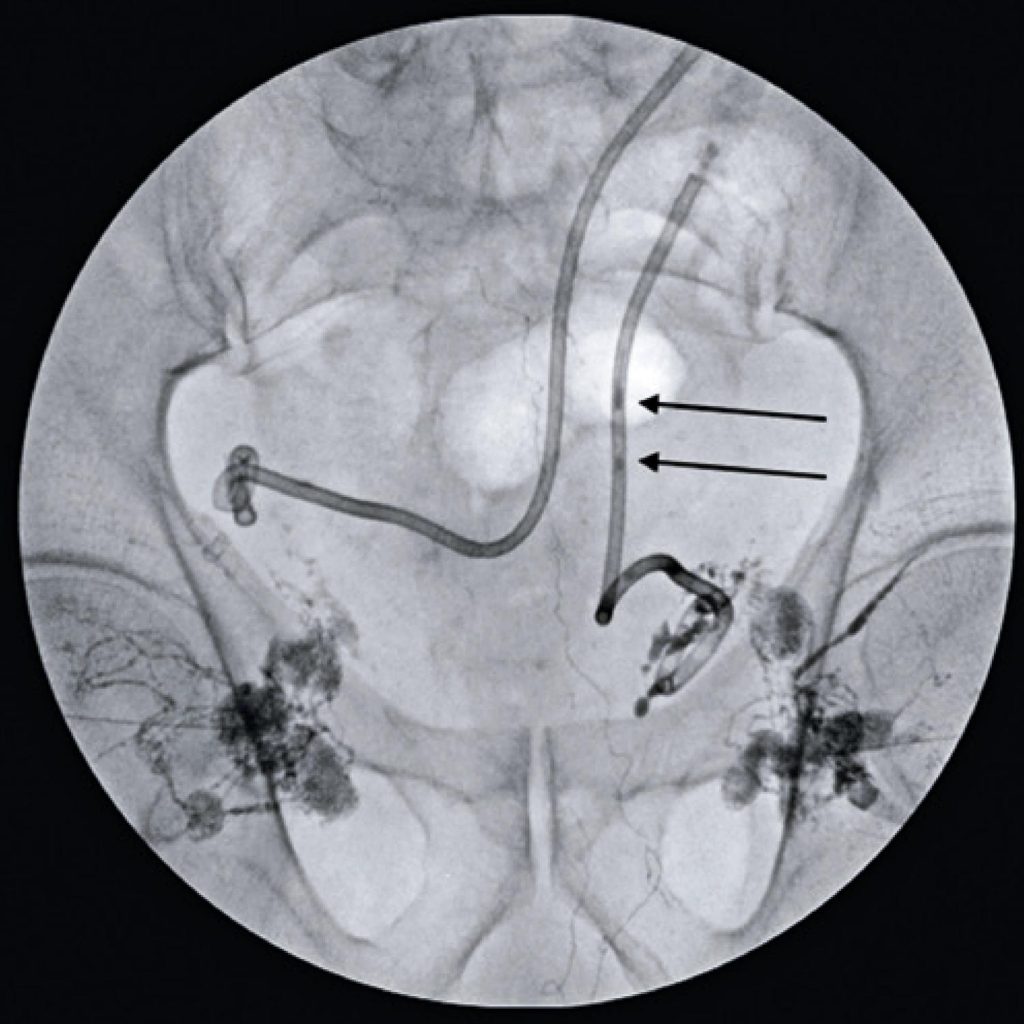

Transafferent nodal embolization for lymphocele treatment: case report

Lymphoceles are collections of lymphatic fluid, mainly caused by major surgical approaches. Most lymphoceles are asymptomatic and limited, but some cases may require a medical management. Among the different techniques, transafferent nodal embolization has emerged as a minimally invasive option, with low morbidity and high resolubility, although it is not widespread in the Brazilian scenario. In this study, we report a case of lymphocele drained percutaneously, with maintenance of high output and requiring transafferent nodal embolization.